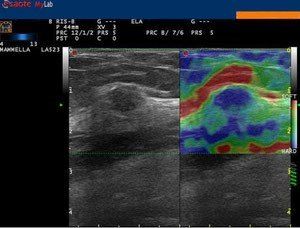

L'elastosonografia è in grado di individuare ad esempio noduli maggiormente sospetti per malignità.

Presso lo studio di ecografia di Campobasso si esegue l'elastosonografia, o elastografia, l'ultima nata tra le applicazioni nel campo della diagnostica ad ultrasuoni. Essa si affianca alle applicazioni tradizionali dell'ecografia, come l'ecocolordoppler, aumentandone l'efficacia diagnostica, in quanto in grado di fornire informazioni sul grado di elasticità o di durezza di un tessuto o di un nodulo, rispetto ai tessuti sani circostanti.

Essa si basa sul principio secondo cui la compressione del tessuto in esame, esercitata dalla sonda ecografica, produce una distorsione, minore nei tessuti duri, quali quelli neoplastici o fibrotici, e maggiore in quelli soffici.